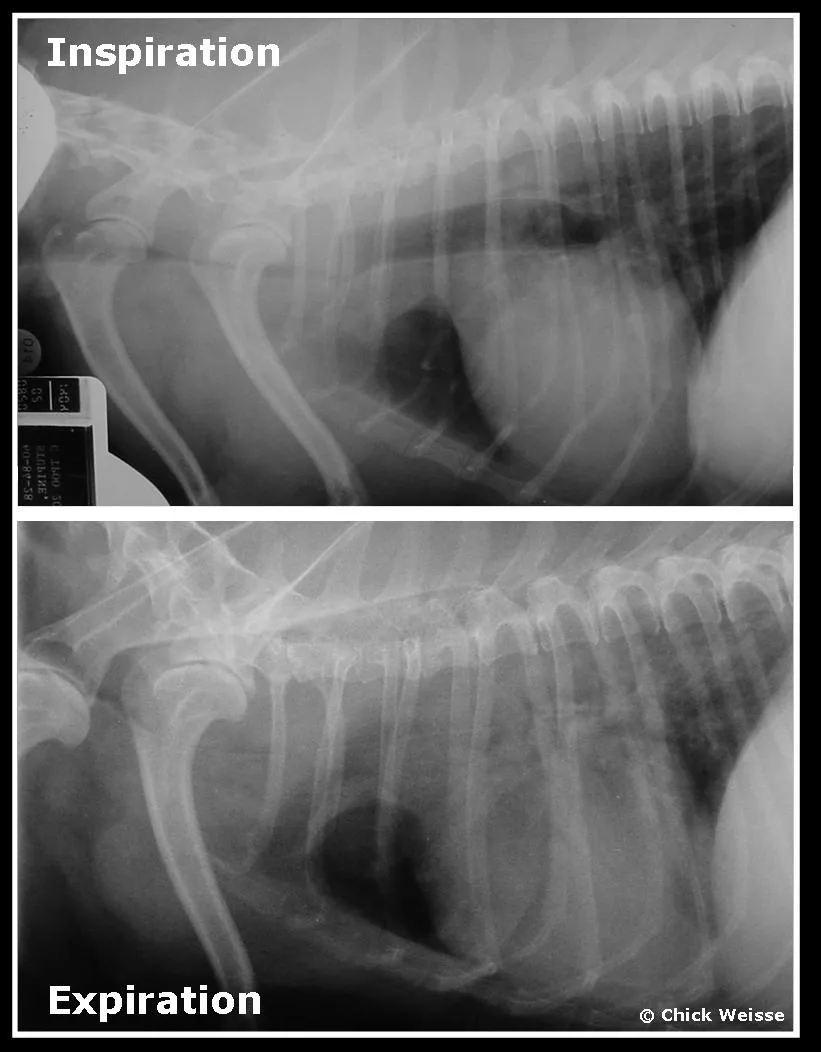

Rings or stent. Whether to use rings (A) or a stent (B) remains one of the most difficult and controversial decisions to be made during treatment of tracheal collapse. The decision is ultimately based on individual factors; however, some basic guidelines can be followed (Table 2). In general, extraluminal tracheal ring surgery is associated with high risk in the immediate postoperative period. Patients typically have a good recovery from stent placement; however, there is potential risk for stent fatigue and fracture in these patients over the long term. Regardless of the treatment used, a comprehensive discussion with the client is important to ensure that what the surgery can and cannot accomplish is clear. Tracheal collapse is progressive, and all current treatments are purely palliative.